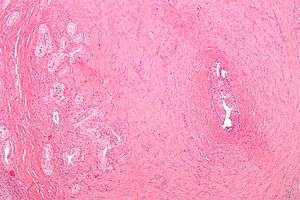

| Micrograph of vasitis nodosa (left of image). H&E stain. | |

Vasitis nodosa is a complication experienced in approximately 66% of men who undergo vasectomy.[1] It is a benign nodular thickening of the vas deferens, in which small offshoots proliferate, infiltrating surrounding tissue.[2] It can be mistaken for low-grade adenocarcinoma by pathologists,[3] and is implicated in late vasectomy failure.[2]